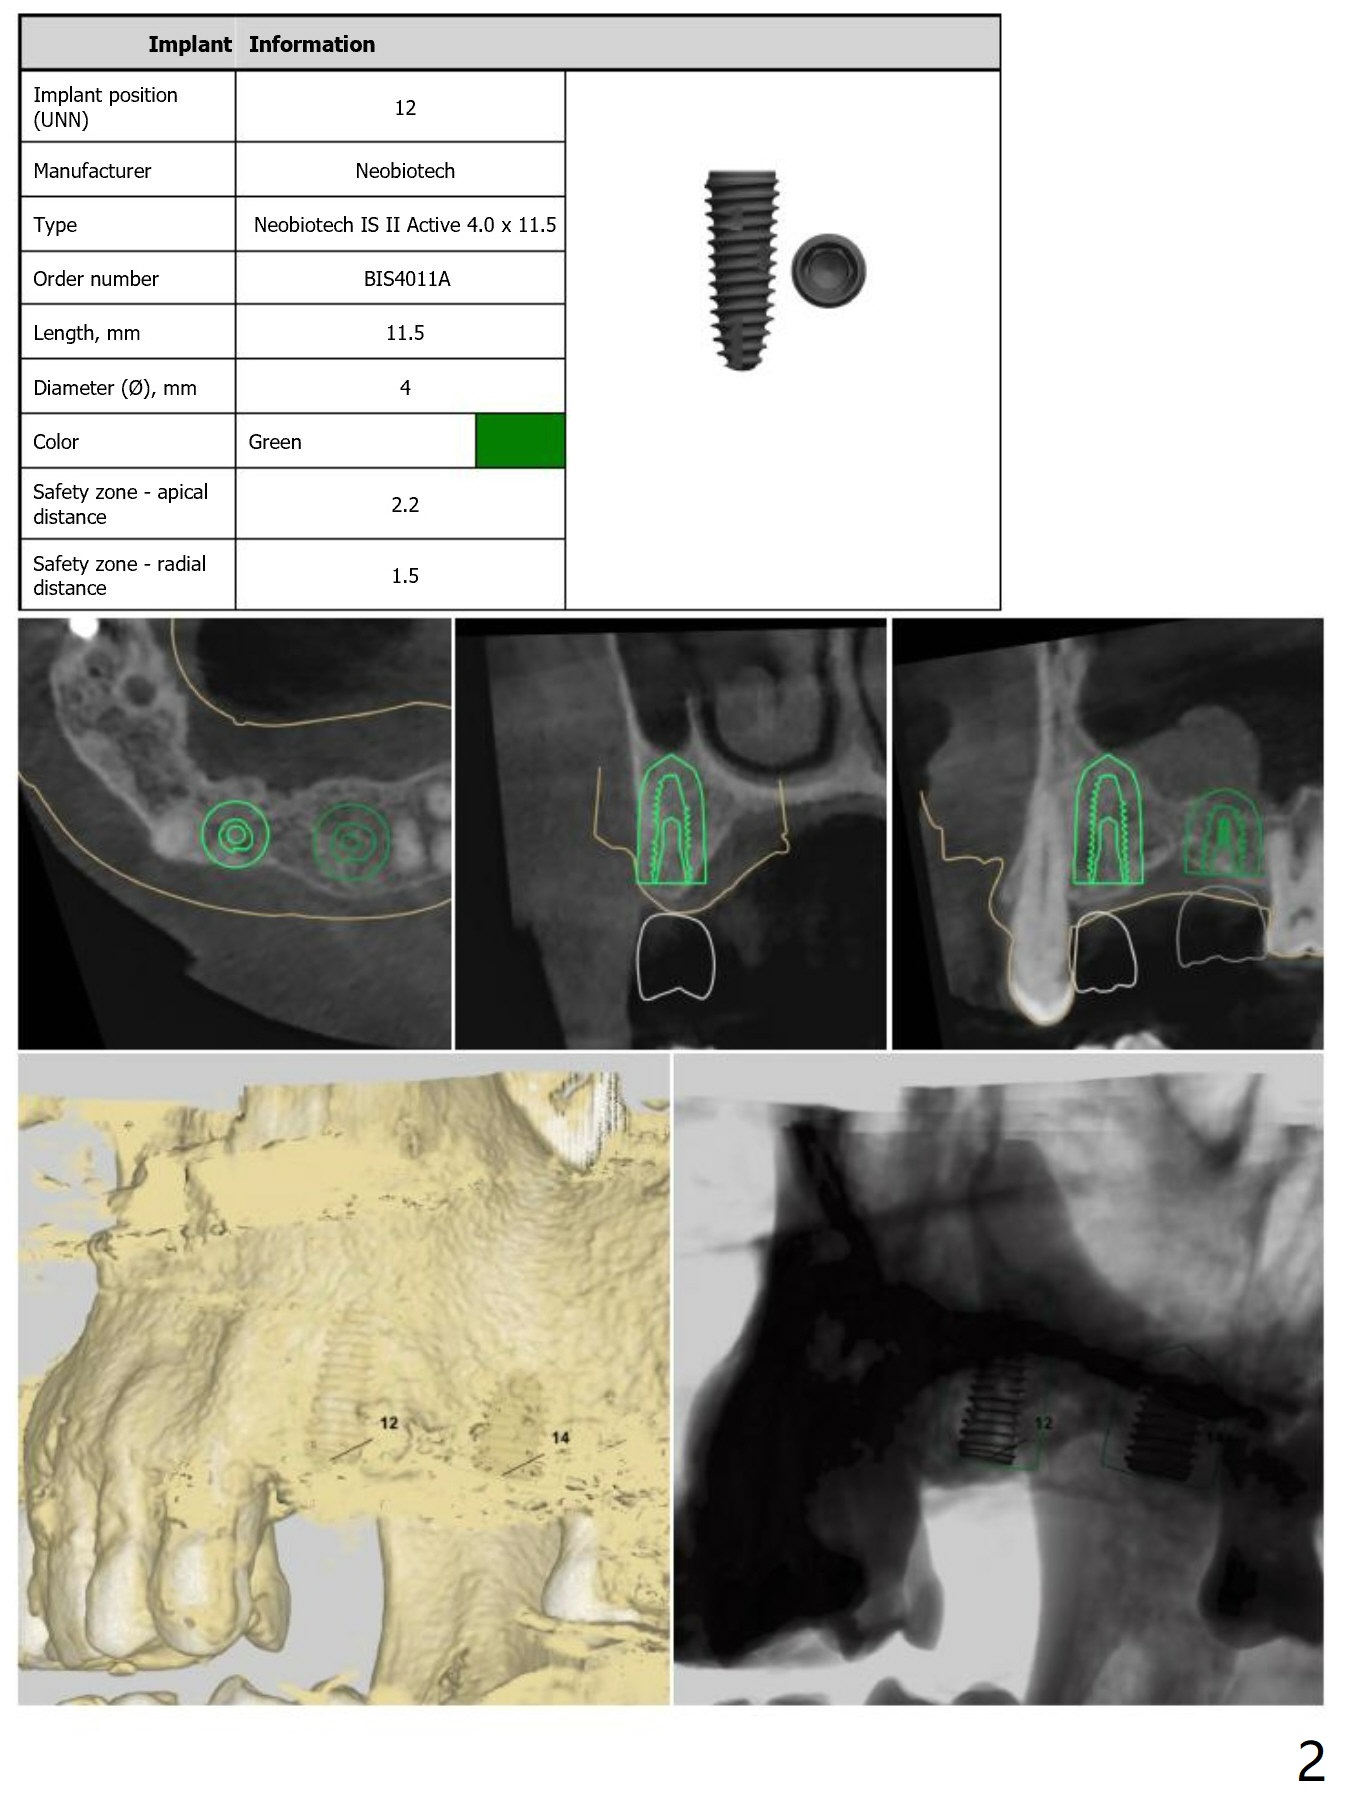

Return to Upper Molar Immediate Implant, Armaments